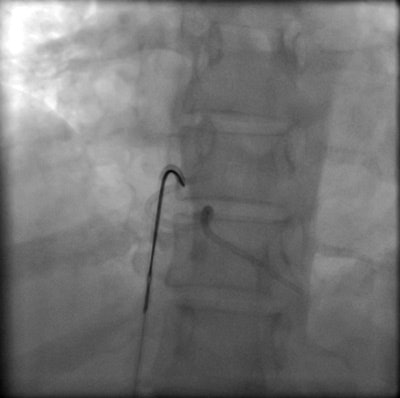

Percutaneous retrieval of the retained fragment of the fractured portacath catheter was successfully accomplished on the second attempt. Following prepping of the right groin, the right femoral vein was punctured and an 8 French sheath was inserted. Selective catheterization of the right ventricle was performed using a 6 French catheter. A 25-mm snare was used to capture the migrated retained fragment. It was then removed successfully without immediate complications.